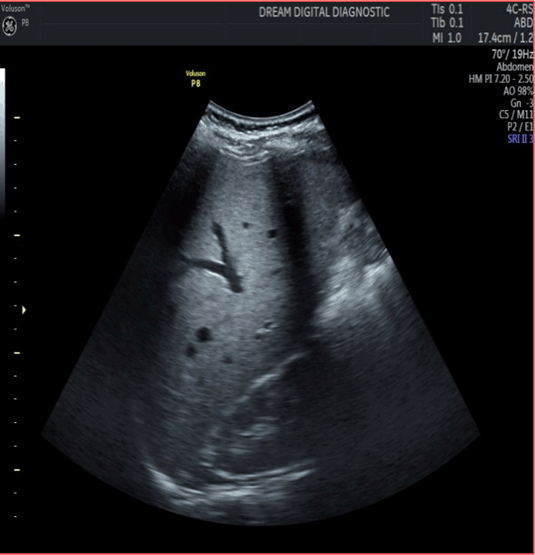

Figure 1: (A and B) : Sonography showing “serpentine” echogenic focus with peripheral halo within the main trunk of the intrahepatic portal vein.

We report a case of a 53-year-old male patient, who presented with complaint of two months history of vague abdominal pain and nausea. There were no other associated symptoms. The results of his complete blood counts parameters were essentially within normal limits. Erythrocyte sedimentation rate was 65 mm/hour. Liver function test and renal function test parameters were also within normal limits. Chest X-ray result showed no abnormality. Fasting lipid profile was essentially within normal limits. Abdominal sonography revealed “serpentine” echogenic focus with peripheral halo in keeping with adult ascaris lumbricoides within the main trunk of the intrahepatic portal vein.Repeat sonography done on the 14th day after 7 days of oral albendazole 400mg administered once daily showed complete disappearance of the adult worm devoid of residual focal lesion. We report this case due to its unique and rare presentation, and also to emphasize the need to consider heminthiasis among the differential diagnosis of focal hepatic lesion in helminthiasis endemic region. This report further repatriates the need for medical therapy rather than overzealous invasive and surgical approach as the first-line treatment for uncomplicated intrahepatic ascariasis (Figure 1), (Figure 2).

Figure 2: Repeat sonography of the liver on 14th day, after one week of medication.

Global estimates indicates that more than one billion infestation due to ascaris lumbricoides exist. The incidence is disproportionately higher in developing countries of south America, Asia and Africa [4]. The prevalence of ascariasis is directly associated with poor hygiene in the setting of low socioeconomic condition [3],[4]. The incidences are exacerbated by malnutrition, the parasitic load and the peculiar parasite biology [4]. Despite high incidence of ascariasis in underdeveloped countries such as sub Saharan Africa, extra intestinal complications such as partial or total obstruction of the hepatobiliary tree and pancrease is uncommon [5]. Intra hepatic ascariasis with focus within the hepatic parenchyma is extremely rare [6]. This case report illustrates the importance of sonography in both diagnosis and monitoring treatment of intrahepatic ascariasis. The finding of living worm as evidenced by display of slow “serpentine” motion within the main trunk of the hepatic vein in this report underscores the value of sonography in establishing the diagnosis of ascariasis within hepatic parenchyma [7]. Sonography is a diagnostic tool of choice in developing countries characterized by dearth of expertise and facilities for invasive and more expensive investigations such as Endoscopic Retrograde Cholangio- Pancreatography (ERCP) or intravenous cholangiography [8]. The ERCP is also an invasive procedure that requires expertise to perform, sonography on the other hand is noninvasive, relatively inexpensive, easy to operate and readily available in developing countries. On sonography, ascaris lumbricoides appear as tubular, echogenic, nonshadowing structure, often containing a thin, longitudinal central sonolucent lines. It also has the advantage of monitoring response to anti-helminthic medication [5],[6],[7],[8]. Unless intra hepatic ascariasis is complicated by abscess where surgical drainage may be necessary, antihelminthic medication is the treatment of choice [8], [9]. In the index case, the patient had oral Albendazole 400 mg once daily for one week. The sonography feature of “serpentine” echogenic focus that occupied the main trunk of the intrahepatic portal vein with peripheral halo as shown in Figure 1, disappear after medication as shown in Figure 2. Surgical procedures are favoured for parasites within the bile duct, as the death of parasite from anti-helminthic medication can result in necrotic focus and risk of stone formation; consequently, recurrent suppurative cholangitis, abscess or sepsis can occur. Ascaris worm possess high glucoronidase activity that deconjugate bilirubin and subsequent stone formation. The risk of helminthes-related hypersensitivity reaction is also increased with dead worms in ectopic focus, as it can result in development of urticaria, dyspnoea, and bronchial asthma. Endotoxins present in adult worm could also lead to ascaridian encephalopathy that often manifest as epileptic seizures, feverish saccade or irritability [3],[6],[9]. Other laboratory parameters were within normal limits. As observed in the index case, hypereosinophilia is often absent; it is usually elevated at initial stages of infestation during early larval migration [8],[9]. The abdominal pain and nausea regressed remarkably within three days of medication in the index case. No feature suggestive of helminthes-related hypersensitivity, cholangitis, abscess or sepsis from necrotic focus was observed after two months of follow-up.